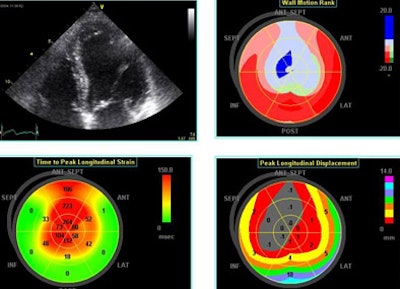

Still, "strain is more than just a number, it's a complex mathematical tensor that linear components that stretch in three dimensions," Thomas said, including linear strain and sheer strain, which can be followed by monitoring clusters of speckles. In one example, low-level exercise showed an increase circumference of strain in a normal volunteer from -16% to -25%. "This can now be integrated in three planes to give us the wall motion rank," Thomas said. Greenberg et al demonstrated that the Doppler-derived myocardial systolic strain rate is a strong index of LV contractility (Circulation, January 2002, Vol. 105:1, pp. 99-105).

![]() |

| Echo software demonstrates (clockwise from upper right) wall motion rank, time-to-peak longitudinal strain and peak longitudinal displacement in a patient with an LAD infarct. |

Left ventricular torsion is a potentially important measurement that can be performed with 2D speckle tracking, or with Doppler tissue imaging per Notomi et al, whose results were well-correlated to MRI measurements (Circulation, March 8, 2005, Vol. 111:9, pp. 1141-1147).